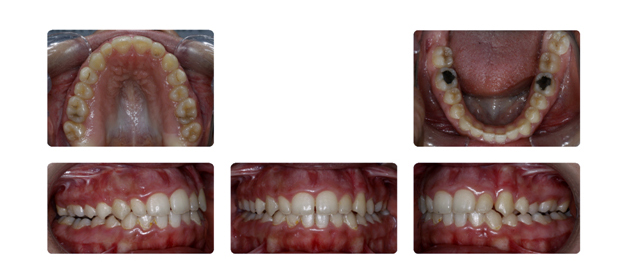

| فک پایین بیمار جلوتر از فک بالا قراردارد وهمچنین دندانهای فک بالا پشت دندانهای پایین قرار گرفته است ودندانهای نیش فک بالا بصورت نهفته می باشد: |

![]() |

| دندان نهفته ی نیش سمت راست در قسمت کام وسمت چپ در زیر لب و بالای دندانها قرار دارد که توسط جراح لثه روی آن برداشته شده وتوسط ارتودنسی و براکتها به جای برده می شود: |